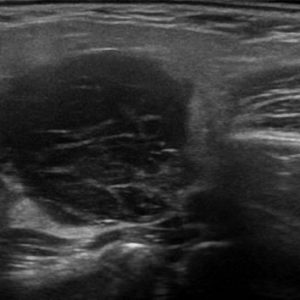

U tuyến nước bọt

Lượt xem: 131» 19-01-2021 -

U tuyến nước bọt

Lượt xem: 102» 19-01-2021 -